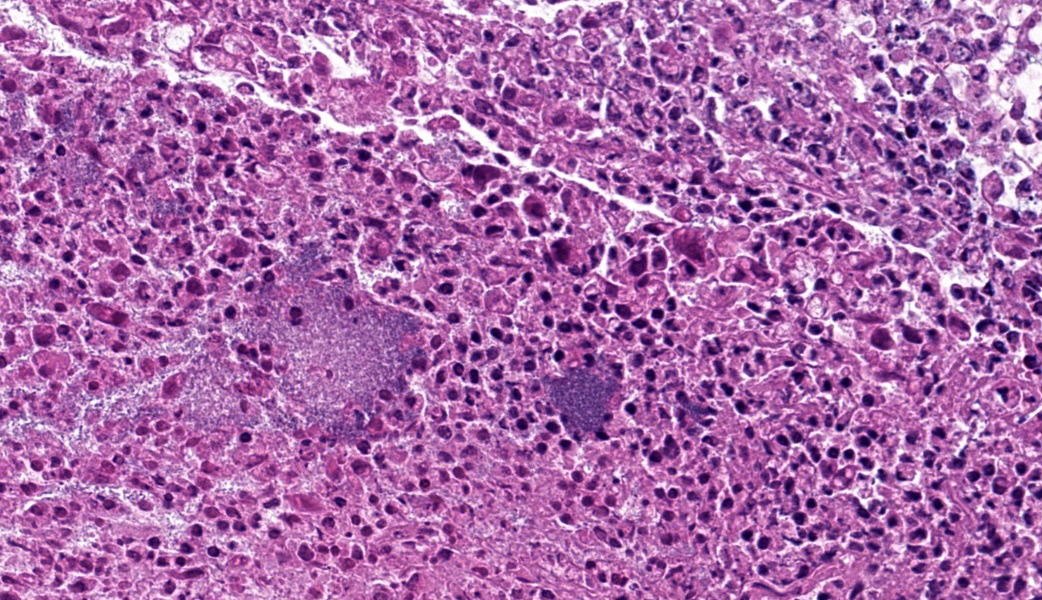

Microscopic Description:Large intestine (Colon ascendens): Multifocal to coalescing, a thick layer of fibrin, sometimes intermingled with degenerated neutrophils, and abundant coccoid to rod-shaped bacteria are attached to the mucosa. In these areas, the mucosa is diffusely destroyed (necrosis) and replaced by fibrin, cell debris and fewer coccoid to rod-shaped bacteria. The lamina propria and the submucosa show a moderate infiltration with neutrophils as well as fewer lymphocytes and histiocytes. The few remaining crypts are dilated and some of them contain neutrophils and cell debris. Some capillaries and venules contain fibrin thrombi or are dilated and filled with neutrophils.

Mandibular lymph node: Lymphoid follicles are indistinct as a result of a severe lymphocyte depletion and replacement by aggregates of epithelioid macrophages with abundant eosinophilic cytoplasm.

- Colon: Colitis, necrotizing, subacute, diffuse, severe, with Peyer?s patch depletion and numerous coccobacilli.

- Lymph nodes: Lymphoid depletion, diffuse, severe.

Due to the degree of necrosis and inflammationin the submitted section of colon. some participants had difficulty deciding in which segment of the GI tract this sample originated. The presence of occasional intact crypts and multiple lymphoid follicles were helpful in establishing an anatomic location of ?intestine? (remember, there are no lymphoid follicles in the stomach except in severe cases of Helicobacter spp infection in some species), but it can be challenging to get further than ?intestine? when a section is as inflamed and necrotic as the tissue is in this case.

There was discussion on the difference between lymphoid necrosis and lymphoid depletion, the former of which implies active targeting of lymphocytes while the latter can be an aftermath of lymphoid necrosis or can be a separate process secondary to any number of pathogeneses (i.e. SCID). The target cell for porcine circovirus-2 is macrophages, and a classic case of PCV-2 may result in granulomatous lymphadenitis, an unusual result of most viral infections. Lymphocytes are not directly targeted in the pathogenesis of PCV-2 but are rather secondary victims to the inflammation from immune response to the virus, making this case a great example of lymphoid depletion. This is further exacerbated in cases of secondary bacterial infection when the offending bacteria colonize Peyer?s patches, which is an important step in the pathogenesis of enteric salmonellosis.